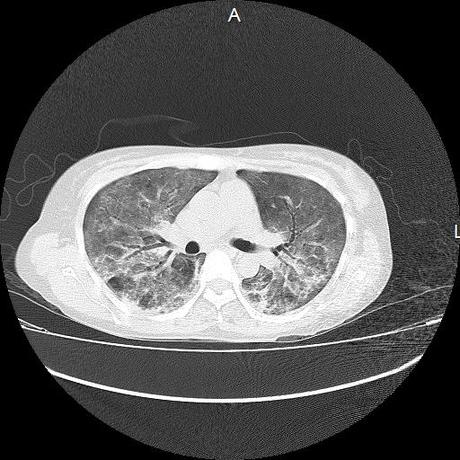

El parénquima pulmonar con areas parcheadas difusas en vidrio despulido combinadas con otras areas hipodensas de baja atenuación debidas a atrapamiento aéreo y engrosamiento intersticial y zonas de fibrosis de predominio en lóbulos medios e inferiores de ambos pulmones.

- LOS HALLAZGOS PUEDEN ESTAR EN RELACIÓN A NEUMOPATIA INTERSTICIAL PROBABLE ETIOLOGIA HIPERSENSITIVA VS AUTOINMUNE/BACTERIANA/FUNGICA.